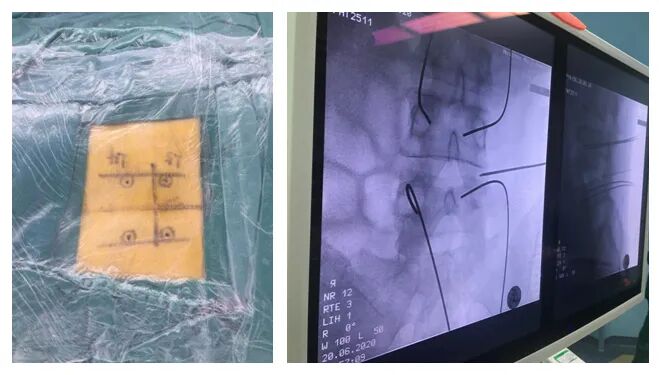

術(shù)前定位

術(shù)中透視

PE-TLIF技術(shù)是一種微創(chuàng)椎間融合技術(shù),手術(shù)方案為經(jīng)椎間孔入路,使用上關(guān)節(jié)突導(dǎo)向切除裝置定向磨除上關(guān)節(jié)突,擴(kuò)大椎間孔區(qū)域,在直徑僅7毫米的脊柱內(nèi)窺鏡輔助下進(jìn)行腰椎的減壓、椎間植骨及融合器植入,最后輔以經(jīng)皮置入椎弓根螺釘。該技術(shù)通過較小的創(chuàng)傷,既能達(dá)到與開放腰椎減壓融合手術(shù)同樣的臨床效果,又能減少并發(fā)癥,實(shí)現(xiàn)病人快速康復(fù)的目的。